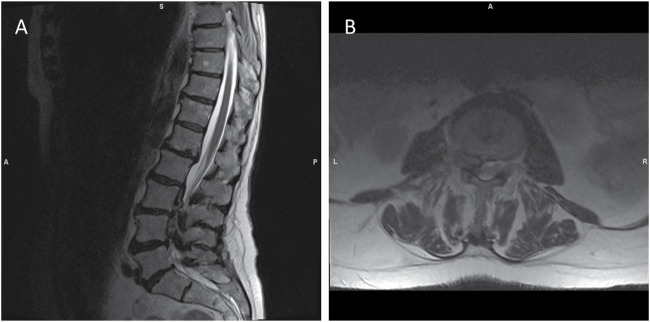

Case description: A 79-year-old woman with a 3-year history of low back pain presented with severe left-sided pain and mobility impairment. Initial examination showed lumbar tenderness and normal muscle strength. Computed tomography (CT) and magnetic resonance imaging scans revealed a calcified extradural mass occupying the anterior portion of the lumbar spinal canal, most likely associated with the posterior longitudinal ligament. The patient underwent L3-L5 hemilaminectomies and dorsal spondylodesis, removing a whitish intraspinal mass. Histopathology confirmed CPPD. Post-surgery, the patient experienced initial pain relief but required emergency surgery due to complications. Over the next year, her mobility and pain improved significantly.

Discussion: Spinal CPPD manifests with varied clinical presentations, complicating diagnosis. Imaging reveals calcifications ranging from deposits to mass-like lesions causing compression. CT provides detailed visualization of characteristic calcifications, aiding in diagnosis, while histopathology remains the gold standard. Multidisciplinary collaboration is vital for accurate diagnosis and optimal management.